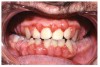

Gingival overgrowth may be associated with the administration of calcium-channel blocking agents, phenytoin, and cyclosporine.13-16 The mechanisms responsible are unclear, but they appear to be related to altered calcium metabolism and concomitant poor oral hygiene-related inflammation.13While the enlarged tissue is usually firm and painless, it may interfere with mastication; and, with significant inflammation, the patient may report pain and gingival bleeding (Figure 9 and Figure 10).

Fig 9. Calcium-blocking Agent-induced Gingival Overgrowth.

Figure 9